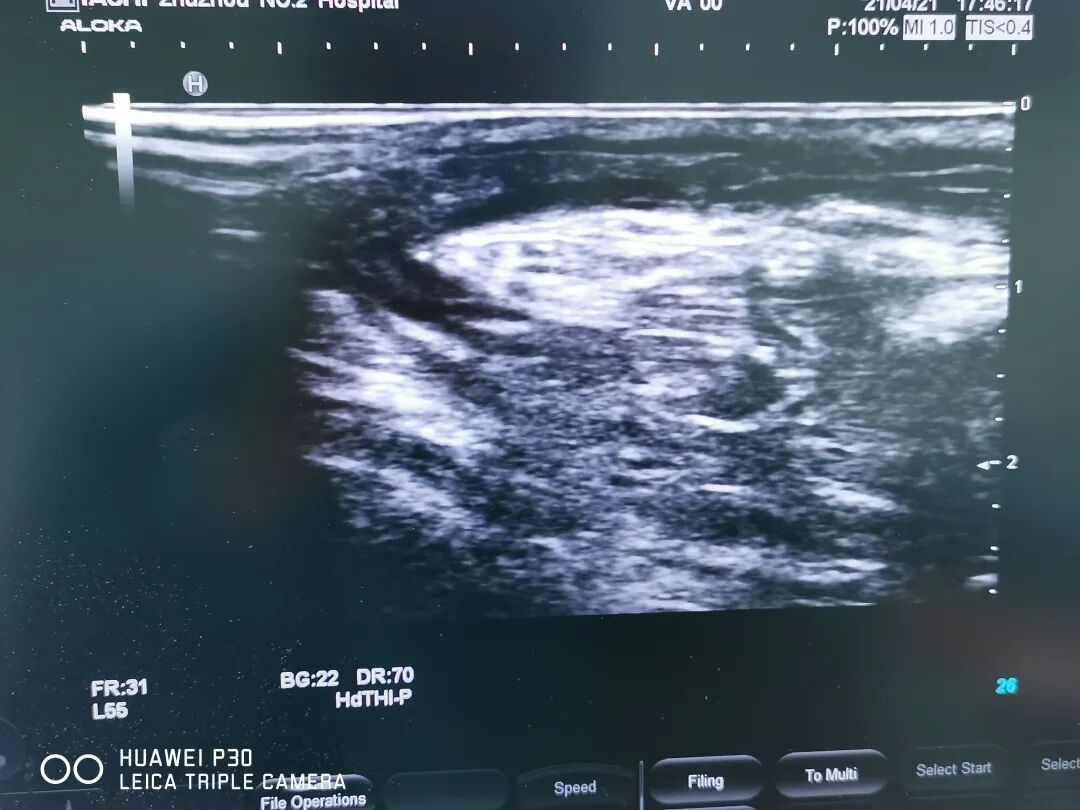

患者術(shù)前

天亮后患者用了將近四個小時的車程趕到!陳醫(yī)師經(jīng)仔細(xì)的體查后,判斷內(nèi)瘺血栓形成并堵塞,立即辦理住院。彩超證實(shí)長段血栓閉塞伴嚴(yán)重內(nèi)膜增生硬化,是我科迄今為止擬行PTA手術(shù)解決的最嚴(yán)重的病變。